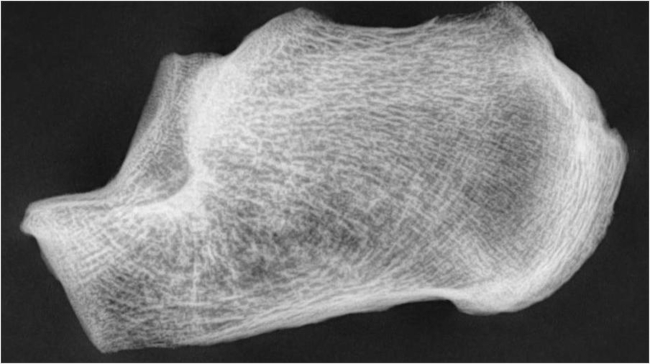

Fase V (normal): Las trabéculas compresivas y tensiles se encuentran normalmente distribuidas (►Fig. 2).

Fase IV (normal): Se nota la ausencia del sector medio del grupo compresivo primario, observándose solo dos pilares, uno superior y otro inferior.